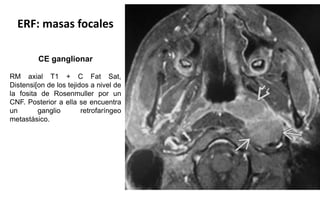

ERF: masas focales

CE ganglionar

RM axial T1 + C Fat Sat,

Distensi[on de los tejidos a nivel de

la fosita de Rosenmuller por un

CNF. Posterior a ella se encuentra

un ganglio retrofaríngeo

metastásico.